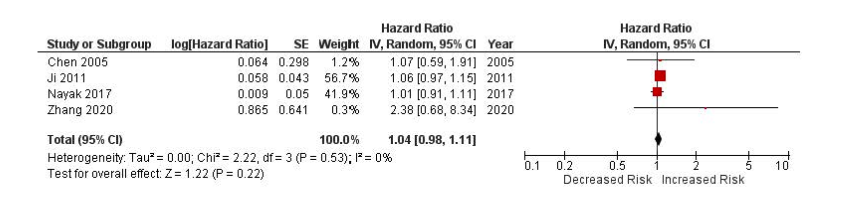

Hsieh and @NamrataRheum

Cancer Survival in RA

Unable to do meta-analysis due to lack of data

HR for lung cancer in RA 1.04

No clear evid of increased risk, but more data and studies needed

Great research project by a high school student (!!)

@RheumNow https://t.co/Sfrf2v2UO4

Eric Dein ericdeinmd ( View Tweet)